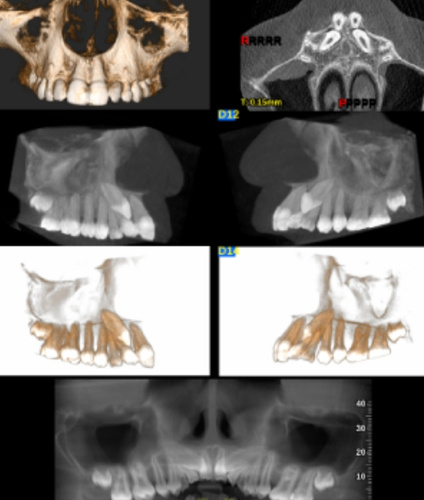

CBCT is a specialized type of CT scan designed for dental and maxillofacial imaging. It uses a cone-shaped X-ray beam to produce high-resolution 3D images, allowing for precise assessment of bone structures, tooth orientation, and soft tissues. This technology is particularly beneficial for complex cases where conventional 2D X-rays may not provide sufficient information.

CBCT is an advanced imaging technique that provides detailed 3D images of the dental and craniofacial structures. Unlike traditional X-rays, CBCT captures volumetric data, offering a comprehensive view of the teeth, jaws, and surrounding anatomy.

During a CBCT scan, the patient is positioned in the scanner, and the machine rotates around the head, capturing multiple images from different angles. These images are then reconstructed into a 3D model, allowing for comprehensive analysis of the dental and craniofacial structures.